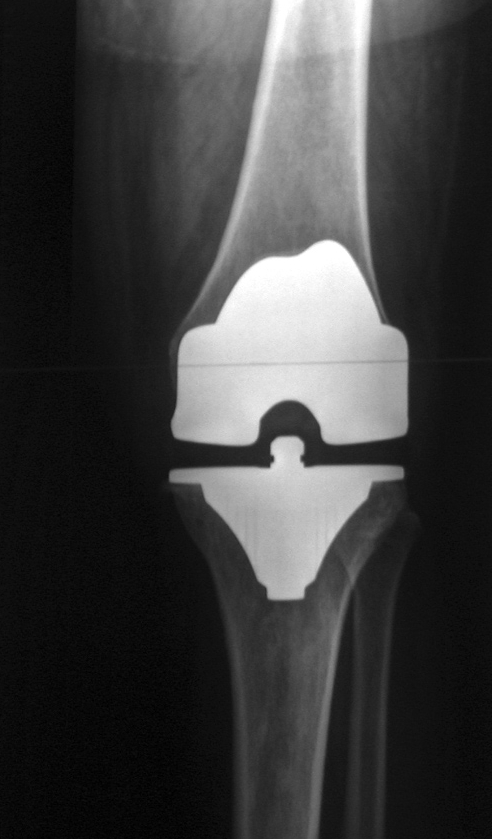

Every year over 1 million hip and knee joint replacements are performed in the US. The decision to have a joint replaced usually does not come easily. Often months or years of pain lead up to the actual replacement. People routinely take higher than advised doses of pain medication, undergo injections (cortisone, Synvisc, or PRP), and some may work through a round or two of physical therapy. Because let’s face it, no one really wants to have a joint replaced. With that in mind, here are 5 things to do to avoid a joint replacement.